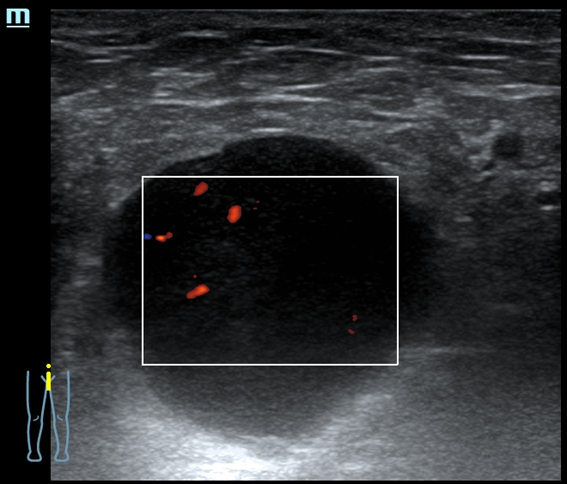

Eco clínica axilar dcha: se visualizan 3 nódulos contiguos de 4,7 x 3,39 cm y 5,4 x 2,9 cm y 5,3 x 3,9 cm. Los 3 con contornos definidos, hipoecoicos, contenido homogéneo, con refuerzo posterior, hipervascularizados,

Ante la sospecha de conglomerados de adenopatías de características tumorales se exploran ecográficamente otras zonas ganglionares visualizándose adenopatías con características tumorales (aumentadas de tamaño, redondeadas, hipoecoicas homogéneas con borramiento de hilio y vascularización cortical) en cuello, axila izquierda y región inguinal izquierda.